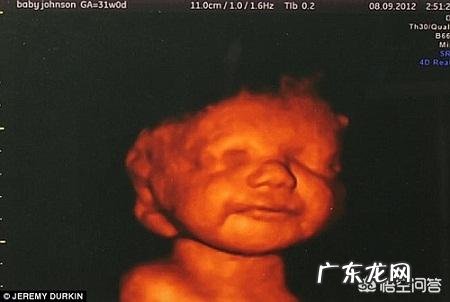

怀孕五个半月,胎儿会笑吗?为什么?怀孕5个半月的胎儿会笑,不仅会笑还会哭,会做鬼脸呢 。

先看1张图片,图片是2010年英国医学家公布的17个周大胎儿在妈妈肚子里微笑的照片,特别震撼 。因为这张照片,被认为17个周大的胎儿已经感知到快乐与痛苦,17个周以后还流产是非常不人道的 。

比如说,B超显示下胎儿会眯眼睛侧耳倾听、或者非常开心地微笑,或者手舞足蹈地跳舞,或者吃大拇指和做鬼脸,或者皱眉头类似不高兴的样子等等 。因此来说,怀孕5个半月的胎儿是会笑的,而且这种笑非常迷人 。

看上图,B超显示下,胎儿笑的多可爱!